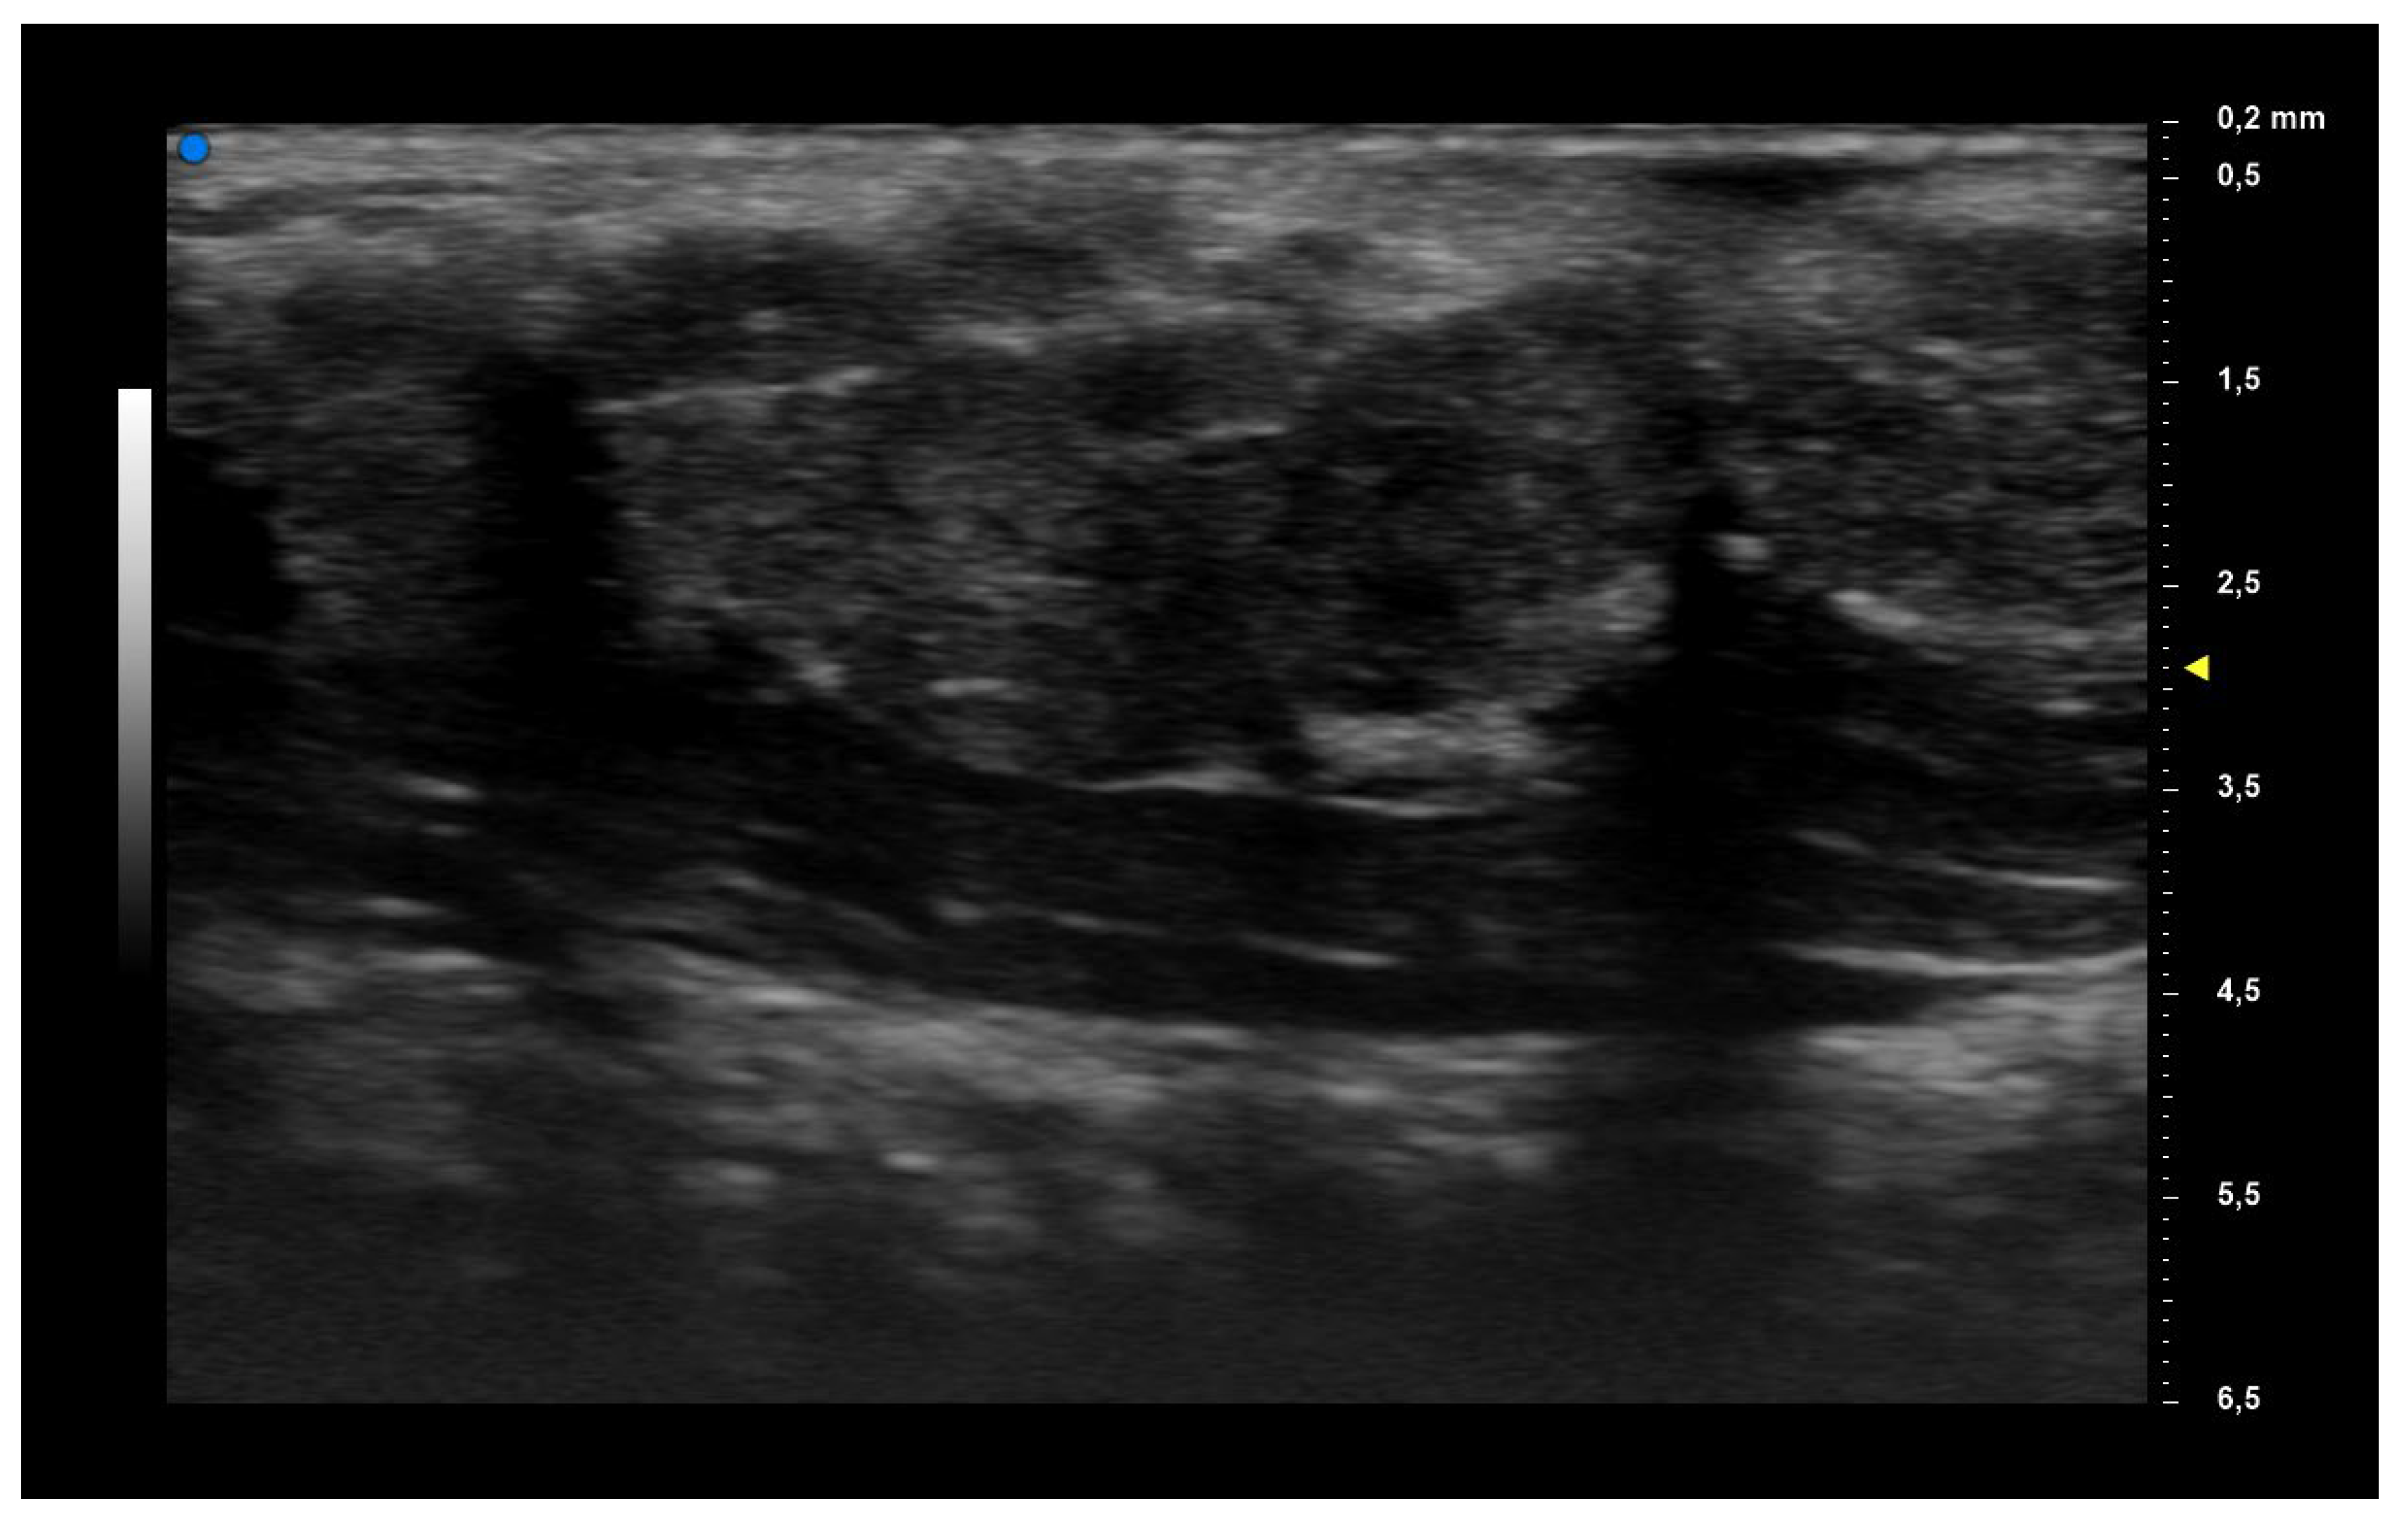

| UHFUS Characteristics | Sicca Syndrome (n = 4) | Parotitis (n = 2) | Non-Sicca, Non- Parotitis (n = 6) | Total (n = 12) |

|---|---|---|---|---|

| Grade 1 | 3 (75%) | 1 (50%) | 4 (67%) | 8 (67%) |

| Grade 2 | 0 (0%) | 1 (50%) | 1 (17%) | 2 (17%) |

| Grade 3 | 1 (25%) | 0 (0%) | 1 (17%) | 2 (17%) |

| Mild vascularization | 1 (25%) | 1 (50%) | 1 (17%) | 3 (25%) |

| Moderate vascularization | 3 (75%) | 1 (50%) | 5 (83%) | 9 (75%) |